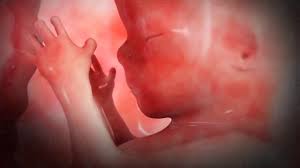

تكو ن الجنين الأسبوع التاسع من الحمل بيبي سنتر آرابيا

تكو ن الجنين الأسبوع التاسع من الحمل أنا مامي

تكو ن الجنين الأسبوع التاسع من الحمل موسوعة